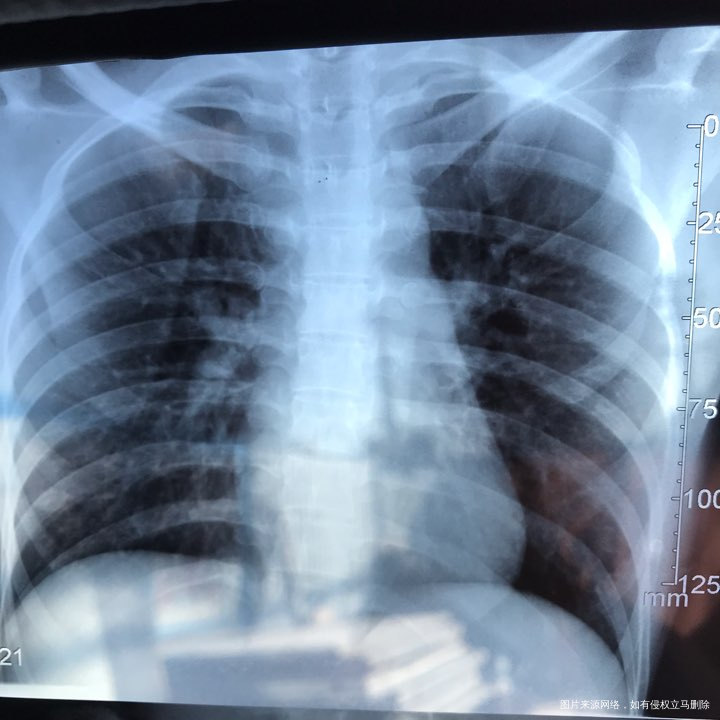

备孕时常1年,前期的检查都做了正常,帮忙看下我的输卵管造影片子吧??

您好,看着像是伞端堵塞了。

您好,考虑输卵管堵塞。建议遵医嘱。

您好,输卵管堵塞,建议切除输卵管做试管,保守保守治疗没有多大意义,觉着我的回复对您有帮助记着帮忙点击采纳,谢谢!